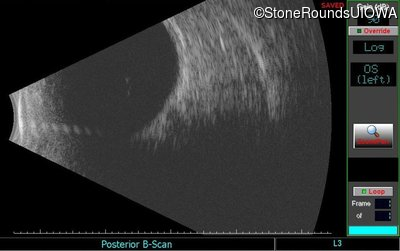

B-Scan Ultrasonography - Left - Hand Motion

Exemplar